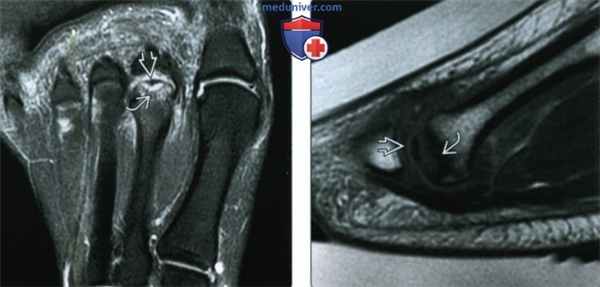

3. МРТ при болезни Фрейберга:

• Отек костного мозга

• Извитая или чашеобразная гипоинтенсивная линия под суставной поверхностью

• Наличие свободных фрагментов возле суставной поверхности

• Вогнутость суставной поверхности головки плюсневой кости

(Слева) При МРТ по длинной оси плюсневых костей на ППВИ определяются признаки болезни Фрейберга: наличие в головке плюсневой кости гипоинтенсивной чашеобразной линии, окруженной гиперинтенсивной зоной. Область субхондрального склероза ЕЯ характеризуется гипоинтенсивным сигналом.

(Справа) У этого же пациента при МРТ в сагиттальной плоскости на Т1ВИ визуализируются изогнутые гипоинтенсивные линии, окруженные зоной, которая имеет сигнальные характеристики жидкости. Область субхондрального склероза гипоинтенсивна при всех последовательностях.